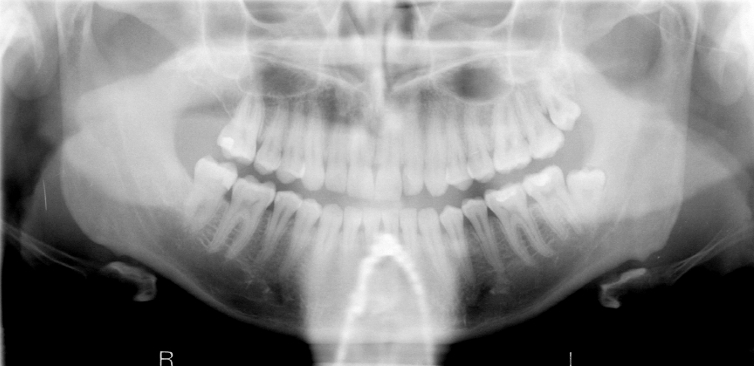

What is wrong with this image?

Too far forward

Anteriors narrowed and blurred; cervical spine superimposed on ramus?